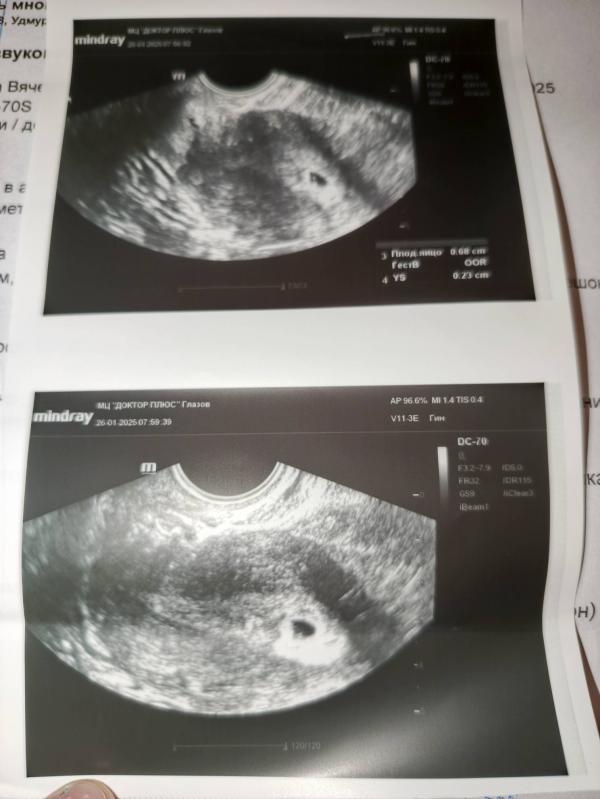

УЗИ показало пя в матке: что это значит? Была ли имплантация вчера? Запись на 9 февраля для прослушивания сердцебиения

post image 1

post image 2

Сходила на узи пя в матке . врач предположила что вчера было ик

Записалась на 9 февраля послушать сердцебиение